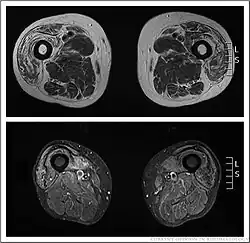

Muscle imaging can help establish the pattern of muscle involvement and selection of a biopsy site.[1]